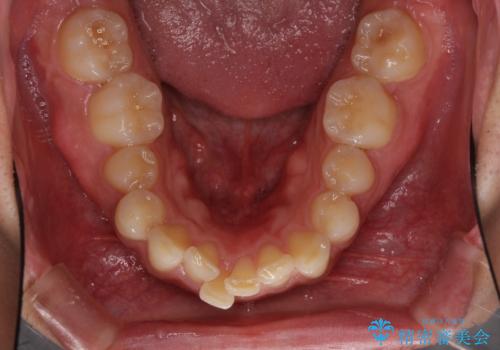

- 深い咬み合わせと前歯のデコボコ、奥歯の欠損を気にして来院された患者様です。

歯列矯正はインビザラインを使用し、矯正治療中の適切な時期に奥歯の欠損部位にインプラントを埋入することとしました。